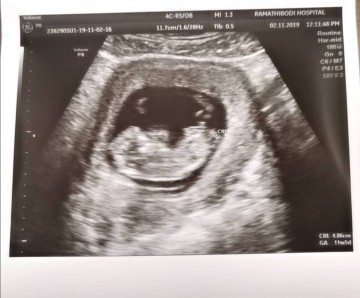

แม่ๆคนไหนมีภาพอัลตร้าซาวด์ประมาณ13วีคบ้างคะ ของเรา13วีค ภาพแบบนี้ค่ะ ดูไม่ออกเลย?